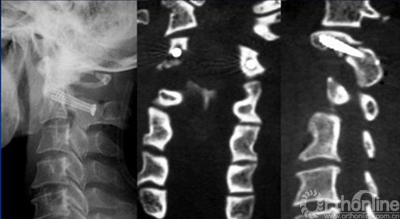

脊柱的椎弓根螺钉内固定虽然是一种具有明显生物力学优势的内固定技术, 但由于脊柱的解剖变异的存在,采用统一的植钉标准显然是不恰当的,每例手术均应根据每个椎弓根实际X线和CT测量结果来置钉,才能提高手术成功率,降低风险。对每一个不同的椎弓根施以相应的不同的置钉方式越来越成为临床十分关注的课题。为此,我们将逆向工程原理与快速成型技术相结合, 设计了一种个性化的数字化导航模板辅助术中实际植钉,并取得了一些积极的成果。现就颈、胸、腰椎等不同节段椎体的导航模板的设计及其应用做一介绍。

通过Geomagic studio12参考最佳进钉点所在的位置,提取椎体后部解剖形态,设计与椎板后部解剖形态一致的反向模板(图2),与椎弓根植钉通道拟合为一体,形成带有定位定向管道的数字化导航模板。在三维重建椎体模型上即可以进行虚拟植钉手术操作。再通过光固化成型技术(SLA)生成实模板体即可以辅助术中应用。在临床应用时可以确保每一枚螺钉正确的置入位置和方向(图3),真正体现了颈椎椎弓根螺钉置入的个体化原则。我们的临床应用范围已经包括了从上颈椎、胸腰椎到脊柱侧弯矫形等多个方面。

临床研究发现,每个导航模板都和相应椎体后部骨性解剖结构十分贴合,所有椎弓根螺钉置入较为满意。术后CT扫描发现椎弓根螺钉完全位于椎弓根内,进钉点准确、进钉角度恰当,螺钉长度及直径合适,无穿破椎弓根皮质及椎体前方的螺钉,患者无周围组织损伤症状。个体化的脊柱椎弓根导航模板对于手术医师只要将模板和暴露的椎板相贴合, 就可以进行钉道准备, 并不依赖于个人经验。模板的制作是个体化的制作, 可采用定制的方式, 因此临床上有应用方便,为颈椎椎弓根的定位提供了一种全新的方法。(如图4、图5)。

图4 术后X线及CT影像